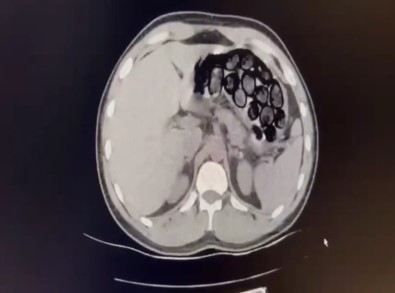

Jandarma ekiplerince takibe alinan Iranli sahis ve beraberindeki 2 kisi, Kars’in Selim ilçesi girisinde ticari takside yakalandi. Yapilan üst aramasinda bir sey bulunamayan Omid Baghernezad, Kars Harakani Devlet Hastanesi’ne götürüldü. Burada çekilen röntgende Omid Baghernezad’in mide ve bagirsaginda kapsüller halinde 65 parça halinde 412 gram sentetik uyusturucu oldugu belirlendi.